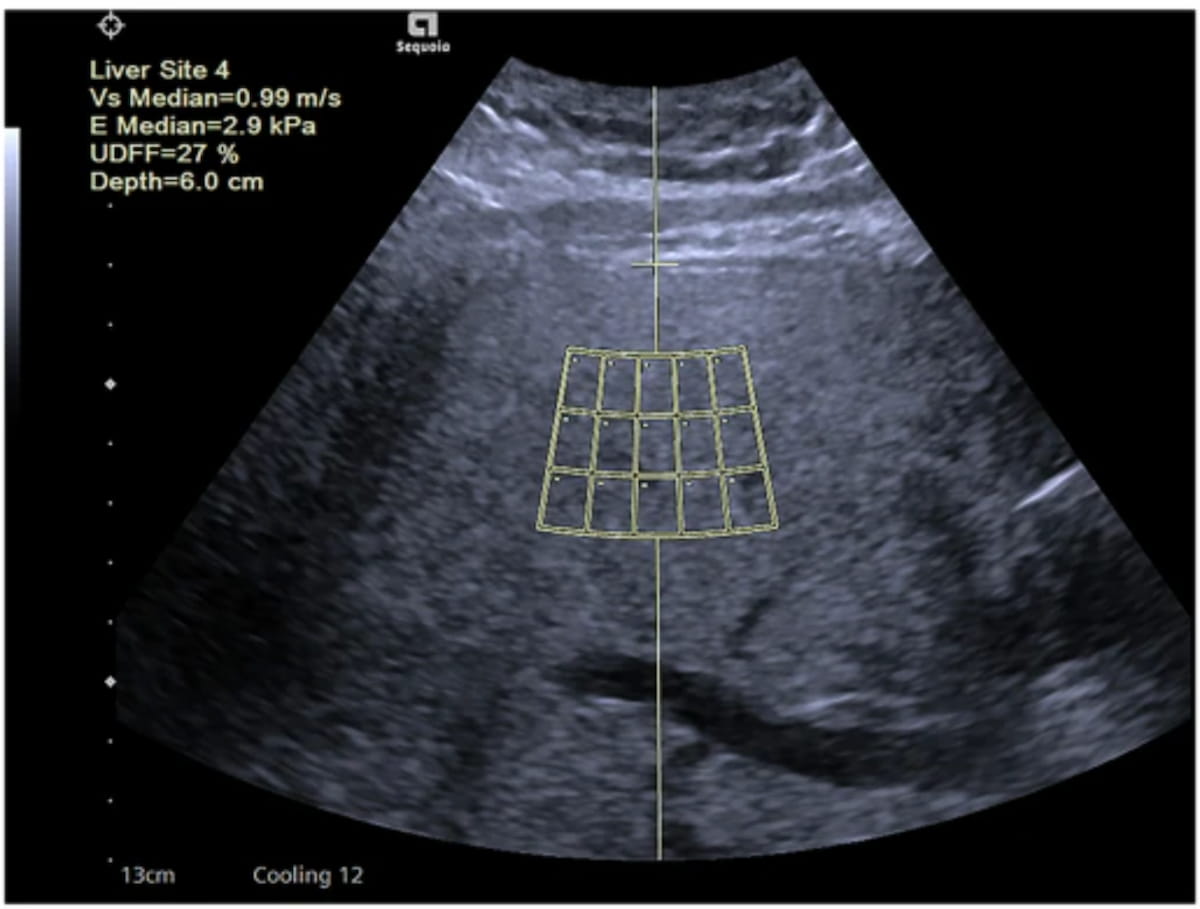

Ultrasound-derived fat fraction assessment offered higher AUCs for differentiating mild, moderate and severe hepatic steatosis in comparison to established noninvasive measures of metabolic dysfunction-associated steatosis liver disease (MASLD), according to new multicenter research.